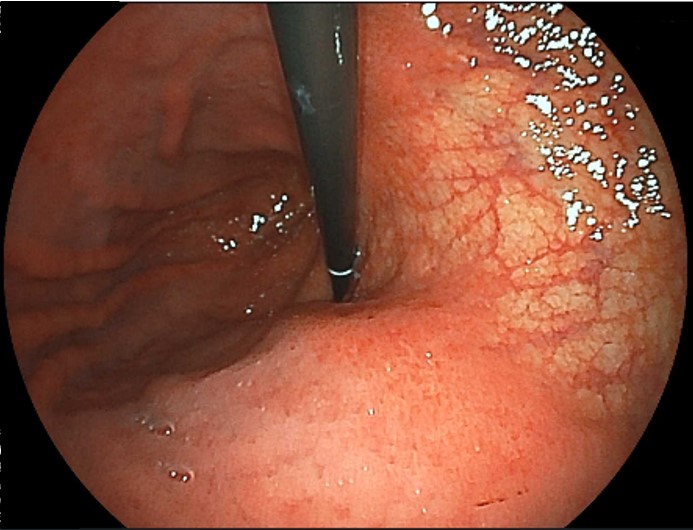

食道カンジダ症

カンジダは真菌(カビ)であり、常在菌です。通常は、感染することはありませんが免疫力が低下していると感染を起こし増殖します。そのため、糖尿病などの既往症がある場合や別の疾患でステロイド治療を受けている場合にはリスクが高いと言えます。感染して増殖すると食道粘膜で白い苔(こけ)のように広がり、胃カメラ検査で簡単に発見できます。つかえやしみる感じといった自覚症状はないこともあります。自然治癒が期待できる場合は経過観察し、症状がある場合には抗真菌薬の内服による治療をおすすめしています。

カンジダは真菌(カビ)であり、常在菌です。通常は、感染することはありませんが免疫力が低下していると感染を起こし増殖します。そのため、糖尿病などの既往症がある場合や別の疾患でステロイド治療を受けている場合にはリスクが高いと言えます。感染して増殖すると食道粘膜で白い苔(こけ)のように広がり、胃カメラ検査で簡単に発見できます。つかえやしみる感じといった自覚症状はないこともあります。自然治癒が期待できる場合は経過観察し、症状がある場合には抗真菌薬の内服による治療をおすすめしています。